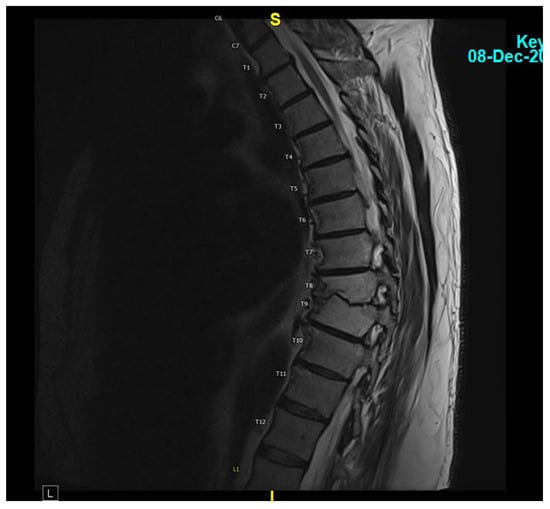

A 62-year-old male with hypertension, type 2 diabetes, atrial fibrillation (on Eliquis), and an L5-S1 spinal fusion 16 years prior developed fever and back pain on 12 May 2023. He contacted a telehealth provider, who ordered a CT scan of the abdomen and pelvis to evaluate for diverticulitis. This imaging demonstrated no diverticulitis but evidence of T8-T9 vertebral osteomyelitis. He was subsequently hospitalized for 8 days, during which he underwent an MRI of the thoracic and lumbar spine with and without contrast, which showed a T8 vertebral fluid collection and diskitis (Figure 1). C reactive protein was 7.70 mg/L with an erythrocyte sedimentation rate of 16. He underwent a CT-guided biopsy of the impacted vertebra and disc. Stains and cultures for bacteria, mycobacteria, fungi, and histopathologic evaluation performed on these specimens were negative. Because of concern for Staphylococcal (Coagulase negative) infection and convenience of administration, he was discharged on an empiric 6-week course of IV daptomycin 800 mg per day (started on 17 May 2023 and completed on 5 July 2023). His CRP normalized to <0.2 mg/dL at the end of treatment. Despite this treatment, his back pain worsened, for which he was prescribed hydrocodone/acetaminophen (Norco) and a muscle relaxer, metaxalone.

Figure 1. MRI thoracic spine with and without IV contrast revealing small T8 fluid collection and possible diskitis T8-T9.